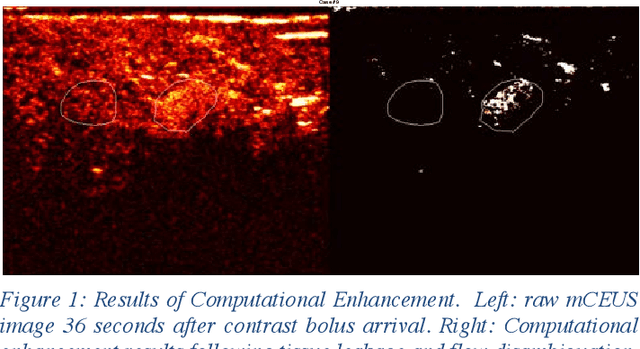

Molecularly targeted contrast enhanced ultrasound (mCEUS) is a clinically promising approach for early cancer detection through targeted imaging of VEGFR2 (KDR) receptors. We have developed computational enhancement techniques for mCEUS tailored to address the unique challenges of imaging contrast accumulation in humans. These techniques utilize dynamic analysis to distinguish molecularly bound contrast agent from other contrast-mode signal sources, enabling analysis of contrast agent accumulation to be performed during contrast bolus arrival when the signal due to molecular binding is strongest. Applied to the 18 human patient examinations of the first-in-human molecular ultrasound breast lesion study, computational enhancement improved the ability to differentiate between pathology-proven lesion and pathology-proven normal tissue in real-world human examination conditions that involved both patient and probe motion, with improvements in contrast ratio between lesion and normal tissue that in most cases exceed an order of magnitude (10x). Notably, computational enhancement eliminated a false positive result in which tissue leakage signal was misinterpreted by radiologists to be contrast agent accumulation.